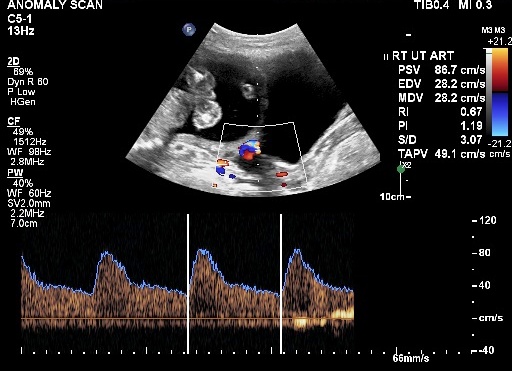

Obstetrics Doppler Study

Doppler study is asked for by the Obstetrician to determine whether the blood flow from the mother to the placenta, and from the placenta to the fetus is adequate. It is also able to detect whether or not the fetus is getting adequate oxygen through blood and whether the fetus is consequently compromised. When indicated, the information sought is important and is intended to enable the Obstetrician take important decisions regarding management of the pregnancy. Our Centres are known for the high level of reliability of Doppler reporting.